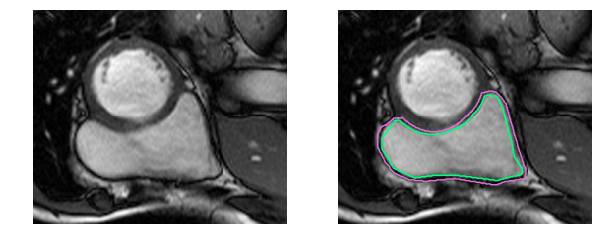

撇开医学术语不谈,要识别RV就更困难了。左心室是一个厚壁圆环,而右心室是一个形状不规则的物体,有薄的壁,有时会与周围的组织混合在一起。这是MRI快照右心室内壁和外壁(心内膜和心外膜)的手工绘制轮廓:

这是一个分割起来很容易的例子。这一个比较困难:

而这对于没有经过训练的眼睛来说完全是一个挑战: